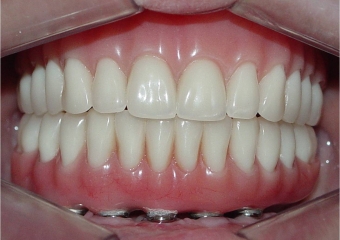

Imagem final

Sorriso final, do caso terminado em setembro de 2013